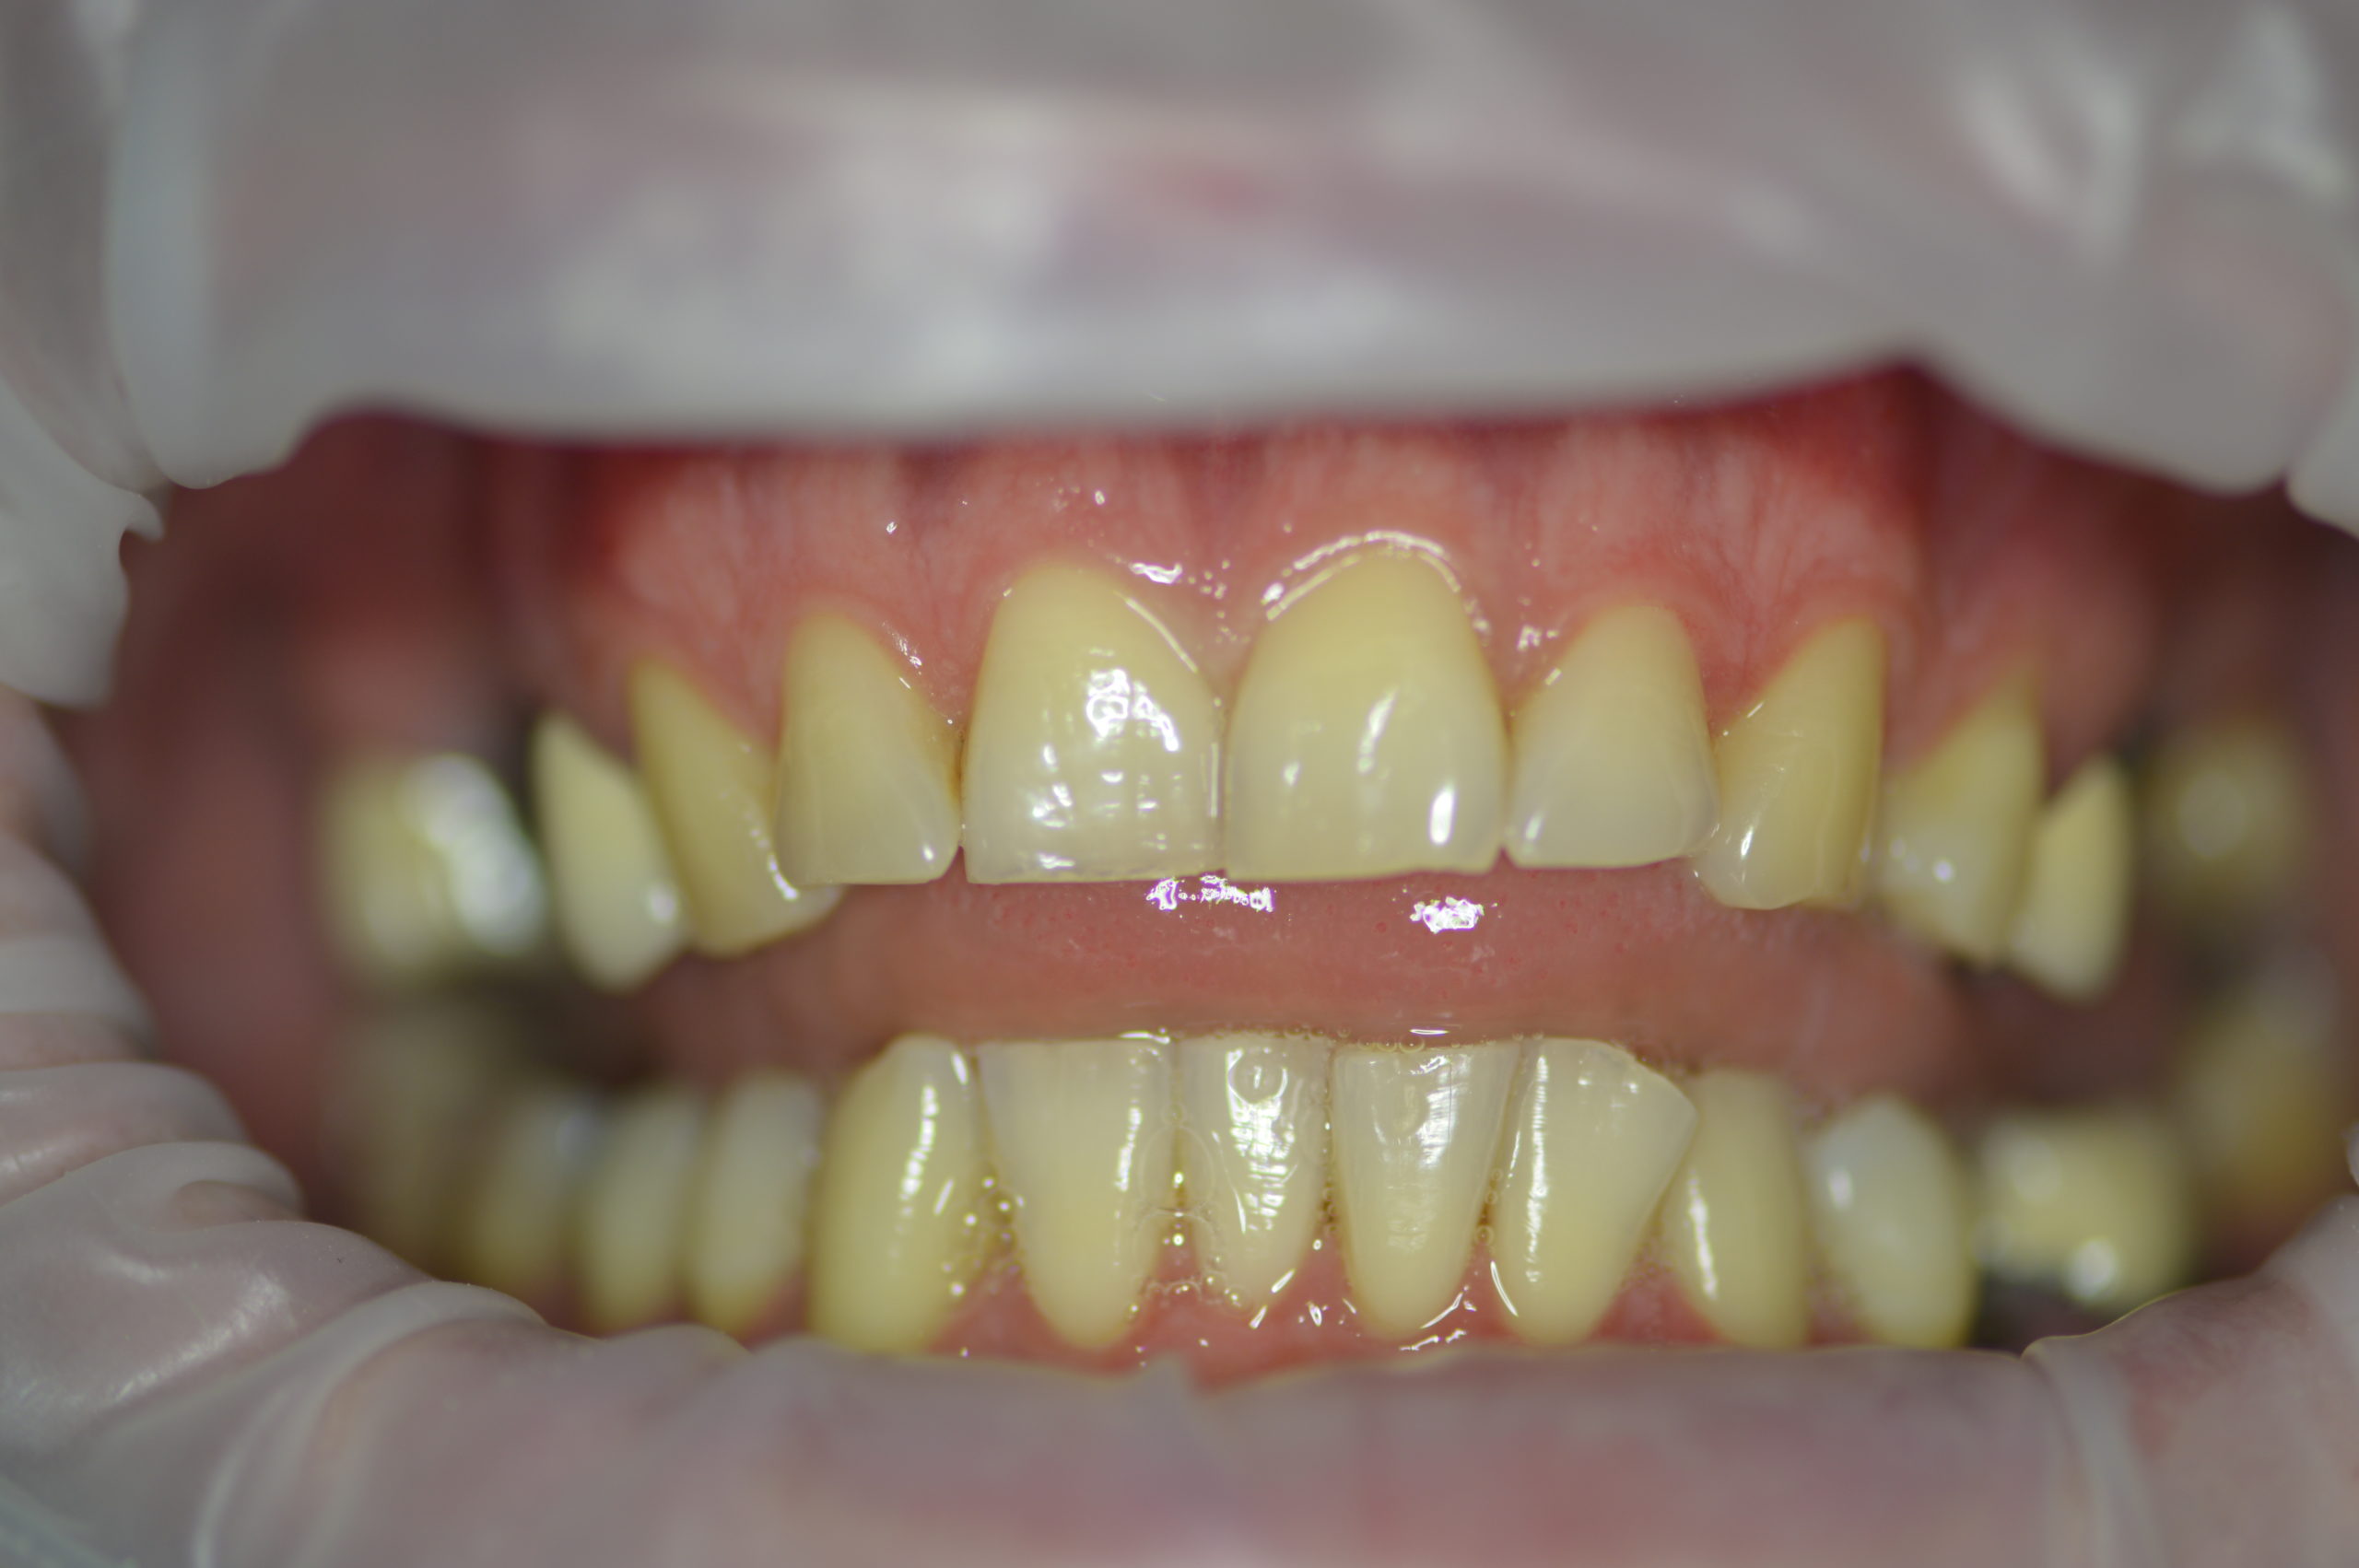

Mr. Peter’s (32 years old) wish was to have nice and bright smile. Dr. Martin has made a treatment plan that contained 6 dental implants (4 for upper jaw and 2 for lower jaw), one tooth extraction, 5 re-root canal treatments and 12 dental crowns. After patient left examination room our staff discussed every detail of treatment with him and Mr. Peter made a booking for implant appointment with Dr.Martin in just 2 weeks after consultation.

The surgery began with the extraction of tooth number 26 and bone graft on upper jaw and it continued with implantation on 27, 26, 16 and 15 on upper jaw and 35 and 37 on lower jaw.

3,5 month after implantation Mr. Peter returned to our dental clinic to continue his treatment with four re-root canal procedures. Doctor decided to gave the implants more time for healing so patient returned in 2 months to get his front natural teeth reshaped and get impressions for his future implant crowns and zirconium dental crowns.

After next visit Mr. Peter left our clinic with this beautiful and natural looking smile. His upper jaw was fully reconstructed using dental implants in combination with dental crowns. Lower jaw was treated with 2 dental implants and two zirconium dental crowns.

Photo BEFORE treatment with dental implants and dental crowns